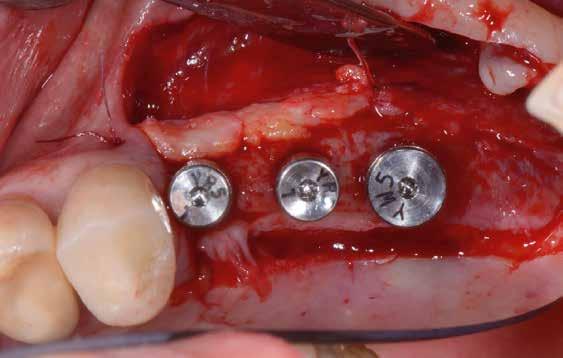

60/40 arányú keverésével történt (5–7. ábra), A-PRF és A-PRF/S-PRF membránokat készítettünk (8. ábra). Az alveólusokat a grafttal feltöltöttük, a felső front régióban vertikális augmentációt végeztünk a tervezett alveoláris csontmagasság elérésének céljából (9–10. ábra). A vertikális augmentáció támogatására titán mikrocsavarokkal rögzített, titánerősítésű teflonmembránokat alkalmaztunk, amelyekre egy rétegben A-PRF membránokat, és egy rétegben A-PRF/S-PRF membránokat helyeztünk. Az alsó állcsont esetében vertikális augmentáció nem volt szükséges, célunk az alveoláris kemény- és lágyszöveti struktúrák prezervációja volt, a graftot csak PRF memb-

ránokkal fedtük. A PRF membránok külön rögzítést egyik állcsont esetében sem kaptak (11–12. ábra). A mukogingivális lebenyt – annak megnyújtása nélkül – a helyére fektettük és varratokkal rögzítettük, per primam sebzárást nem végeztünk. A varratokat 2 hét után távolítottuk el, a varratszedésig a sebgyógyulás támogatására per os 1000 mg/nap C- és 12 000 NE/nap D-vitamint adtunk (28).

teljes mértékben megtartott, a vertikális augmentáció a tervezettnek megfelelő eredményű volt (13–15. ábra), a klinikai kép is ennek megfelelően alakult, optimális menynyiségű keratinizált ínnyel és azt adekvát sebészi technika eredményeképpen megtartott vesztibulummal (16–17. ábra). Az alsó és felső állcsontba 4-4 darab Bredent COPA Sky implantátumot ültettük, D1-D2 csontminőség mellett,

35 Ncm primer stabilitást mértünk. Nyílt gyógyulási protokollt alkalmazva az ínyformázókat is behelyeztük, amelyek körül az ínyt csomós öltésekkel zártuk (18–20. ábra) Amennyiben lehetséges, mindig nyílt gyógyulási protokollt választunk, így biztosítva elegendő időt a lágyrészek maturációjához (29). Kiemelendő, hogy az irodalmi adatoknak (30, 31, 32) és saját tapasztalatunknak megfelelően az íny biotípusának jelentős, pozitív irányú változását észleltük. Az implantátumokra 180 nap gyógyulási időszakot követően (minden implantátum stabilitása Periotesttel –8-as értékű volt) hagyományos lenyomatvételi módszer és egyéni értékű artikulátor használatával a fogtechnikus (D1 Dental Kft., Garamvári Csaba) overdenture típusú fogpótlást készített (21. ábra)